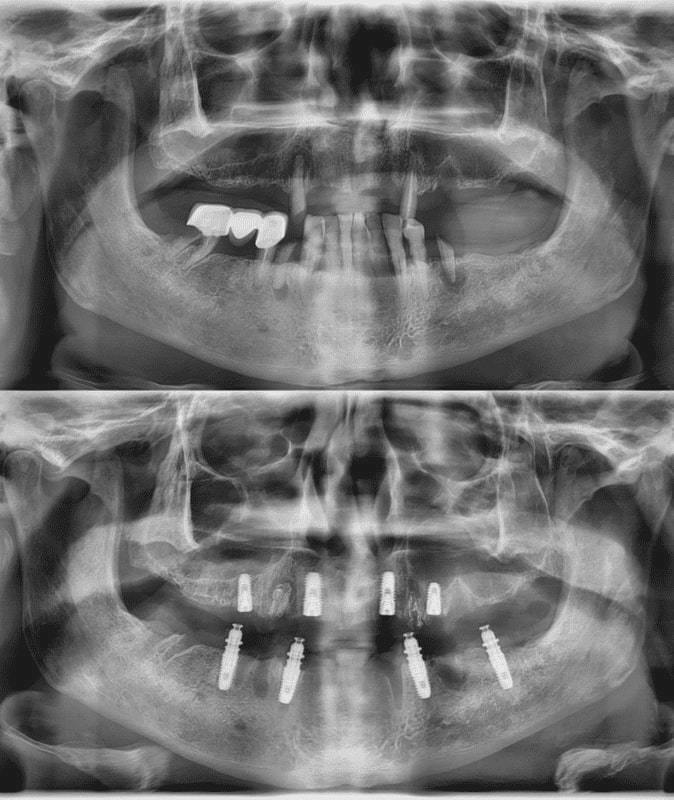

All-on-4 в https://cdiclinic.ru — это способ полного протезирования челюсти, при котором несъёмный протез фиксируется всего на четырёх имплантах. Два импланта устанавливаются в переднем отделе, ещё два — под углом в боковых зонах. Такое распределение нагрузки помогает использовать даже те клинические случаи, где костной ткани недостаточно для классической имплантации.

Хирургический этап включает установку четырёх имплантов. После этого изготавливается и фиксируется протез, который восстанавливает жевательную функцию и эстетику улыбки. В зависимости от клинической ситуации протезирование может проходить в один день или в очень короткие сроки после операции.